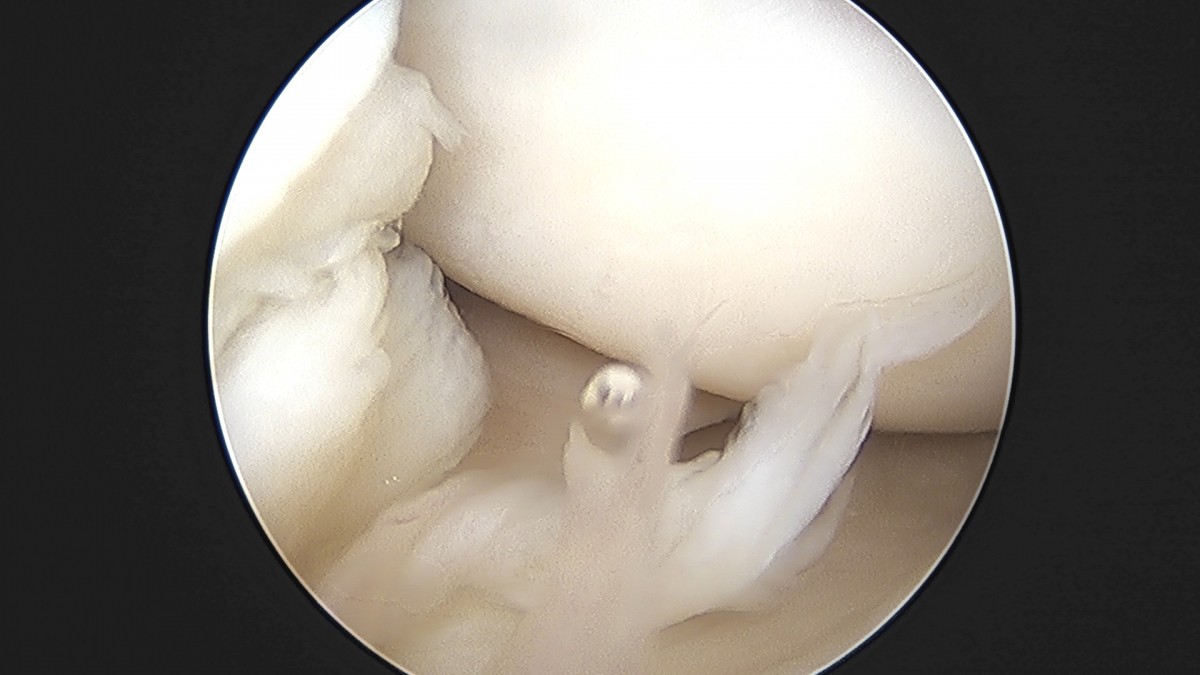

이재상원장님 무릎 낭종 제거술 김은O 환자

작성자 최고관리자 댓글 0건 조회 789회 작성일 25-09-16 15:20